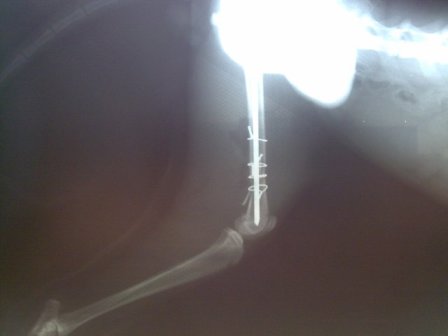

تصاویر جراحی ترمیم استخوان ران شکسته شده گربه (شکستگی چندتایی، 5 قطعه)

رادیوگراف گرفته شده پس از اصلاح شکستگی